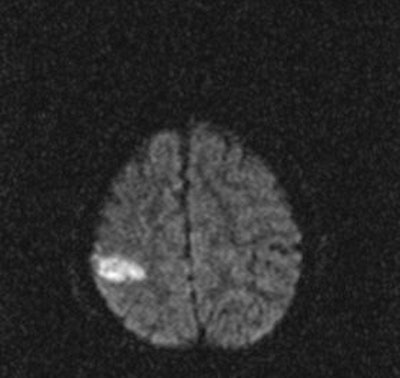

In traditional diffusion-weighted imaging (DWI) for stroke, "you'd look at this for cellular disruption, and you'd see quite clearly the major region affected by the stroke," he said. "DWI is often very broad. In the SWI image, you are seeing evidence of dramatic changes in oxygen saturation and maybe other sources of susceptibility. We can see the source of the stroke and maybe the vascular territory affected (see below). The hypothesis is that the deoxyhemoglobin content of the small vessels has increased over their normal values due to slower or restricted flow, making these (vessels) visible when they would normally not be visible."

![]() |

| Stroke imaging with SWI. Although the DWI image (above) shows the affected region well, the details of the stroke are shown in the SWI image (below). Images courtesy of Dr. Daniel Wycliffe, Loma Linda University, Loma Linda, CA. |